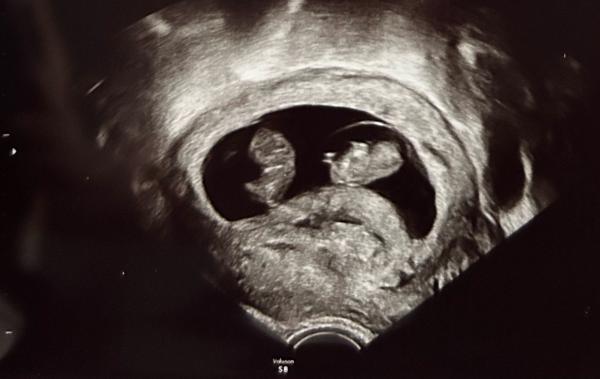

Hallöchen!  Bin recht frisch hier und habe am Montag erfahren, dass wir Zwillinge erwarten 😅🥳 Es ist meine erste SSW und das hat meinen Mann und mich doch ganz schön von den Socken gehauen!  Auf dem Ultraschallbild sieht man ganz leicht die beiden Fruchthöhlen, die FA meinte es wären zweieiige.  Nun habe ich viel gelesen und recherchiert und bin über diese vielen Zwillings-Kombinationen gestolpert 🫣  Nun frage ich mich, ob die beiden doch auch eineiig sein können, sich also jeder in seiner Fruchthöhle befindet und sie sich aber die Plazenta teilen? Und wenn ja, ob die FA das direkt beim US gesehen hätte?  In meinem Mutterpass ist "Monoamniotisch" nicht angekreuzt. Ich bin aktuell 10+1, den nächsten Termin zum Schallen habe ich erst in knapp drei Wochen. Dort wird dann auch der HarmonyTest gemacht.  Sieht man bis dahin dann die Plazenta bzw. zwei? Sodass man auf MoDi oder DiDi schließen kann? Und ist ein Besuch bei der Pränataldiagnostik bei Zwillingen generell notwendig und sinnvoll?   Fragen über Fragen 🙂🥲 Danke schon jetzt für eure Einschätzung oder einfach liebe Worte 🥰🫶🏻

Bild zu Zwillinge - DiMo oder DiDi? - Mehrlinge - für Eltern mit Zwillingen, Drillingen und mehr